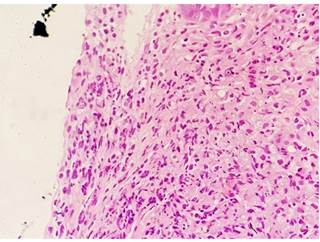

El examen histológico reveló malacoplaquia, caracterizada por agregados de histiocitos granulares, de los cuales varios contenían cuerpos de Michaelis-Gutmann intracitoplasmáticos. Se confirmó histoquímicamente con tinciones periódicas de ácido peryódico de Schiff (PAS) (Figura 7).

Figura 7 Hallazgo histológico que mostró inclusiones de agregados histiocitos y cuerpos de Michaelis-Gutmann con características patognomónicas de malacoplaquia.